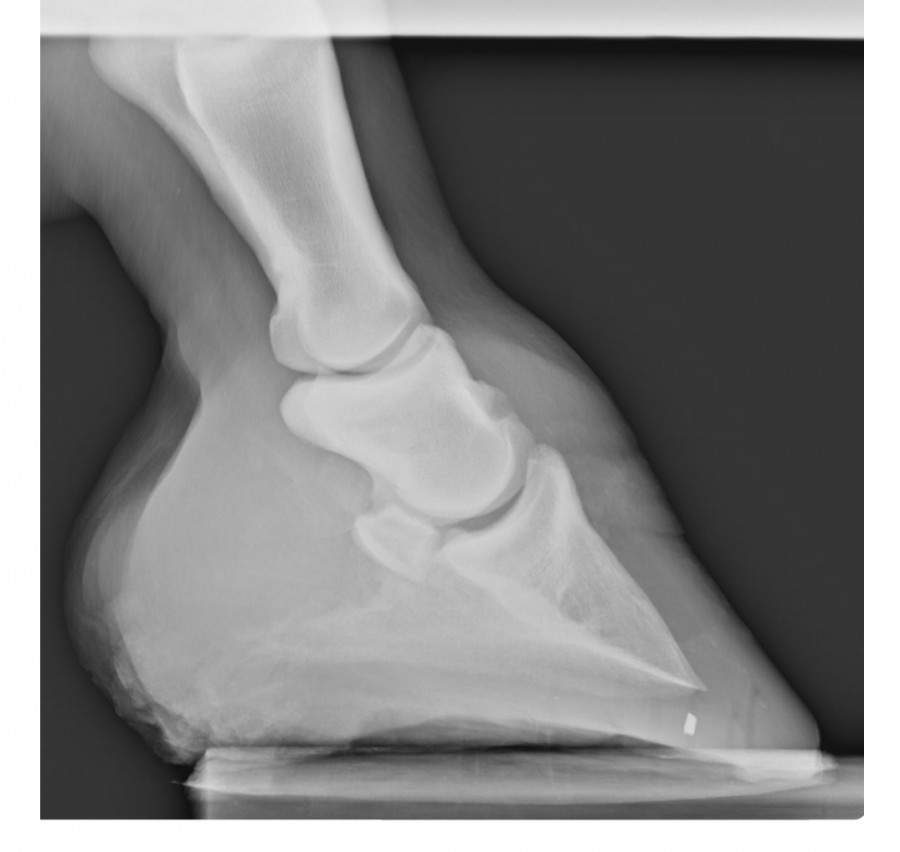

Résultat : arthrose en face antérieure de la 2ème phalange et ossification des cartilages ungulaires. D'après la véto, inutile de faire des radios de l'autre pied. Pour elle c'est sur qu'il y a la même chose, peut-être en moins développé mais présent quand même. C'est parait-il la "maladie des chevaux de trait"

marechal05 Oui j'ai fait des radios de l'antérieur droit en 2017 suite à une boiterie. La véto n'avait pas pensé nécessaire d'en faire de l'antérieur gauche qui d'après elle devait très certainement avoir les mêmes problèmes : arthrose sur la face antérieure de la 2ème phalange et ossification des cartilages ungulaires.

Antérieur droit Mars 2017

Antérieur gauche Septembre 2019